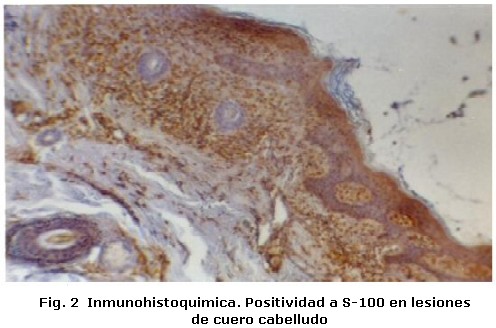

Un varón de tres años de edad con diagnostico de Histiocitosis de Células de Langerhans con afección ósea multifocal y otros sitios especiales fue referido al Servicio de Odontopediatría del Hospital Universitario de Maracaibo por el Servicio de Oncología Pediátrica del mismo Hospital, para valoración. El examen médico reveló, exoftalmos, palidez mucocutánea con pápulas eritematosas, lesiones hipercrómicas en miembros inferiores, dermatitis seborreica en cuero cabelludo, múltiples adenopatías cervicales y otitis supurativa recurrente. El informe de las pruebas de laboratorio indicó anemia y diabetes insípida. La biopsia de cuero cabelludo y el estudio inmunohistoquímico de la muestra tomada (Figura 1, 2 y 3) confirmaron el diagnóstico clínico, mientras que el examen de líquido cefalorraquídeo y médula ósea reportaron ausencia de infiltración. En las imágenes de resonancia magnética cráneo-facial, se evidenció realce anormal sugestivo de infiltración de huesos de base craneana y fosa anterior y media, mientras que la tomografía axial computarizada, reportó ausencia parcial de arco cigomático del lado derecho e imágenes osteolíticas en hueso temporal y pared orbitaria externa del mismo lado, acompañadas de lesiones similares en techo de orbita del lado izquierdo (Figura 4). Otros estudios, como tomografía de abdomen, pelvis y tórax, electroencefalograma, Rx de huesos largos, tórax óseo y columna, no revelaron hallazgos de interés. Durante la evaluación odontológica, la exploración extraoral evidenció exoftalmos y las lesiones de piel antes descritas; intraoralmente se registró la presencia de placa dental, gingivitis y hemorragia (Tabla 1), acompañada de movilidad dental, bolsas periodontales y recesión gingival (Figura 5) en la zona posterior izquierda de ambos maxilares (Tabla 2), además de caries dental y erupción prematura del 26. Radiograficamente se observaron lesiones osteolíticas, de bordes mal definidos, que medían aproximadamente entre 0,5 y 1,5 cm. de diámetro, localizadas en relación al 64, 65, 26, 74, 75, 85, también se observó agenesia de los gérmenes del 35 y 45 (Figura 6). Para el momento de la evaluación odontológica el paciente estaba recibiendo tratamiento con vasopresina y quimioterapia con vinblastina y prednisona. El manejo odontológico incluyo una fase inicial preventiva en la cual se instruyo a los representantes y al niño sobre hábitos de alimentación, higiene bucal y técnicas de cepillado y una fase quirúrgica llevada a cabo bajo anestesia general. Previa valoración sistémica y premedicación con antibioticoterapia se realizaron exodoncias del 65, 26, 74, 75 y curetaje de las lesiones. El resultado de la biopsia del tejido encontrado en los maxilares reportó un infiltrado inflamatorio severo, constituido por acumulo de linfocitos, histiocitos espumosos y células plasmáticas, mientras que el estudio inmunohistoquímico realizado con proteína S-100 y CD1a resultó negativo. Después de dos meses de seguimiento, el paciente cicatrizó favorablemente con persistencia en el 64 de recesión gingival, exposición de dos tercios de la raíz distal y movilidad leve. Radiograficamente se observan signos de osificación en las zonas intervenidas, sin embargo, es necesario seguir monitoreando al paciente para descartar la aparición de nuevas lesiones (Figura 7).

La Histiocitosis es una rara enfermedad cuyas manifestaciones clínicas son muy variadas; en el caso reportado, las características clínicas coinciden con algunas típicamente descritas en la literatura en relación a la edad, dermatitis seborreica, diabetes insípida, exoftalmos y lesiones óseas multifocales1-4. Este último tejido es uno de los más afectados1, nuestro paciente presentó lesiones en ambos maxilares y de forma bilateral en mandíbula, aunque en mayor grado del lado izquierdo. Desde el punto de vista clínico estas lesiones pueden semejar enfermedad periodontal y provocar movilidad dental2, la afectación ósea en nuestro paciente provocó erupción prematura del 26, recesión gingival y grado severo de movilidad dental; situación agravada por la presencia de irritantes locales. Un hallazgo que no hemos podido constatar con la literatura revisada, es la ausencia de los gérmenes del 35 y 45 sin relación con historia familiar, la cual podría catalogarse como agenesia, ya que de acuerdo a la secuencia y cronología dental, a los tres años edad deberían observarse signos de su formación7. Por otra parte, la ausencia bilateral de los gérmenes y la presencia de importantes lesiones osteolíticas solo en relación al 35, descarta la posibilidad de que las células infiltrantes hayan sido responsables de hallazgos similares en el lado contralateral donde la lesión era inferior a 0,5 cm. Sin embargo, es necesario descartar otros factores responsables de la agenesia dental antes de definir su etiología. El estudio inmunohistoquímico realizado a la lesiones intraorales no reveló positividad para S-100 y CD1a, a pesar de haberse encontrado positivos en la biopsia a inicial de cuero cabelludo. Estos marcadores además del CD207 han sido catalogados como específicos para la determinación de células de Langerhans; sin embargo se ha reportado hasta un 13% de resultados negativos para CD1a y un 7% para el CD2078. Los resultados obtenidos en la inmunohistoquímica de las lesiones maxilares, también podrían estar relacionados con los efectos producidos por la quimioterapia sobre las células infiltrantes. No obstante otros factores relacionados con la toma de la muestra no pueden descartarse como responsables de estos hallazgos. La decisión de seleccionar la cirugía, quimioterapia y/o radiación como tratamiento en la histiocitosis, dependen de la extensión de las lesiones, el grado de tejido involucrado y de la presentación unifocal o multifocal1,3. En este caso se decidió realizar exodoncias de los dientes con grado de movilidad severa y curetaje, con el fin no solo de tratar las lesiones maxilares sino de controlar el riesgo de infección. Se concluye que los maxilares al igual que los huesos del cráneo deben ser evaluados en pacientes con diagnóstico de Histiocitocis de Células de Langerhans, ya que estos pueden ser los únicos huesos afectados como sucedió en el caso estudiado. Por otra parte es importante resaltar que a pesar de la importancia de las pruebas inmunohistoquimicas en el diagnostico de esta enfermedad, su resultado siempre debe ser correlacionado con los hallazgos clínicos, radiográficos e histológicos encontrados en cada caso en particular.